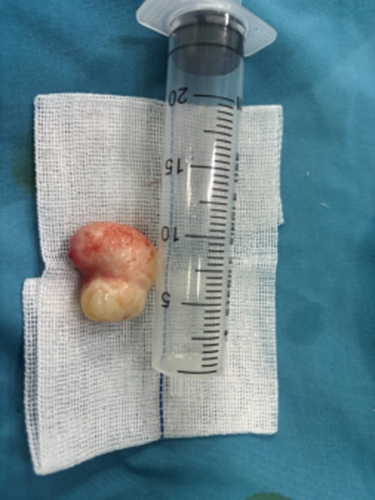

術(shù)后的病理檢測(cè)結(jié)果顯示切除的腫物為良性(鼻息肉)。家長(zhǎng)懸著的心終于放下了。

鼻息肉是一種常見(jiàn)的鼻部慢性疾病,外觀上像新鮮荔枝,表現(xiàn)為一個(gè)或多個(gè)表面光滑、觸之柔軟、半透明的腫物,可以出現(xiàn)在鼻腔和鼻竇黏膜的任何部位。鼻息肉常表現(xiàn)為持續(xù)性鼻塞并呈進(jìn)行性加重,甚至完全阻塞鼻腔通氣,鼻塞嚴(yán)重者表現(xiàn)為閉塞性鼻音、睡眠打鼾、分泌物增多、嗅覺(jué)減退或喪失。一旦治療不及時(shí),就會(huì)導(dǎo)致病情加重,鼻息肉越長(zhǎng)越大,直至填滿整個(gè)鼻腔,最終導(dǎo)致鼻子變形,鼻背變寬,形成了外觀酷似青蛙的鼻子——“蛙鼻”。